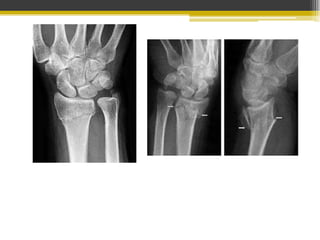

Fractura de la metáfisis distal del radio

A 3 ó 4 cm de superficie articular

Angulación volar de la punta de la fractura

Desplazamiento dorsal del fragmento distal

Puede o no incluir a estiloides cubital

 Caída sobre la mano en hiperextensión

Mantener la longitud radial

 De 6 a 8 semanas

En pacientes con poco desplazamiento o mínima conminución

En Fx conminutas, desplazadas o abiertas no subsidarias de

reducción cerrada ni fijación interna.

Usada en Fx con desplazamiento articular

Yeso postoperatorio según estabilidad

Fracturas de carpo y mano

Fracturas del escafoides

• Es la fractura más

frecuente del carpo con

un 60-70%.

• Estables e inestables

• Durante una caida con la

mano en flexion dorsal.

• Puede ser invisible los

primeros dias.

• Paciente post-traumatismo con dolor a la presion en la region.

• 2 semanas despues se pide radiologia AP, lateeral y oblicua.